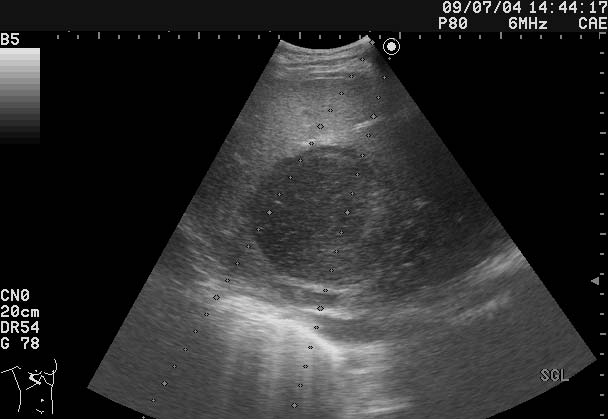

Молодой парень с болями в животе, высокой температурой и симптомами интоксикации

В печени обнаружен очаг

Ваше заключение и тактика?

Абсцесс печени, дренирование

Можно предположить абсцесс печени

Все верно, абсцесс печени

Дренирован, динамика - см по числам в правом верхнем углу сонограмм